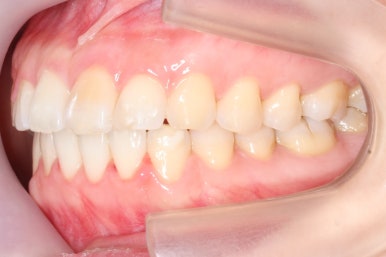

부산앞니교정 키다리아저씨치과에 처음 내원하셔쓸 당시의 입안 모습입니다.

앞니가 살짝 삐뚤어진 것을 볼 수 있고, 삐뚤어진 사이에서 약간의 틈새도 있었습니다.

예전에 치료 받으셨던 앞니 부분에 약간의 변색도 와서 미적으로 좋지 못한 상황이였습니다.